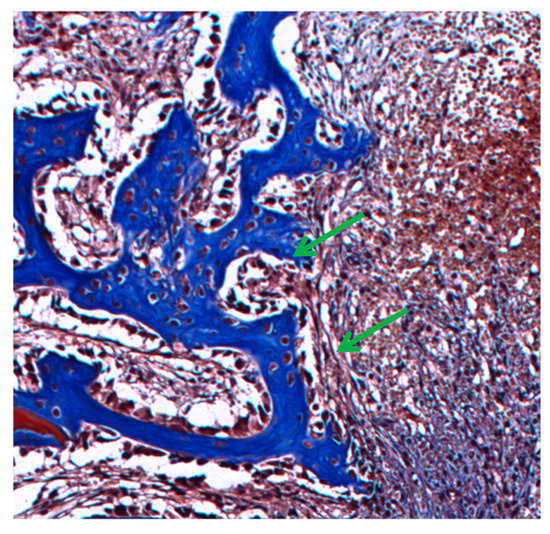

At higher magnifications (Figure 5a,b), granulation tissue is observed in the tissues surrounding the implanted material in the initial periods of 7 and 15 days (Figure 4a,b). This pattern was found for all tested materials. In the granulation tissue it is possible to identify the cells present in the inflammatory infiltrate: mononuclear (blue arrow), polymorphonuclear cells (green arrow), and giant cells (black arrow). Also, collagen matrix disorganization is noted. Figure 5c is from a sample of the 60-day period. Organized tissue with collagen fibers and few cells, mostly fibrocytes (green arrow) and fibroblasts (blue arrow), is observed in the fibrous capsule surrounding the implanted material.

Figure 5.

Photomicrographs of tissue around NRL-AgNP at higher magnificatins: (a) 7 days, (b) 15 days, and (c) 60 days post-surgery showing inflammatory cells and fibrous capsule. See text.